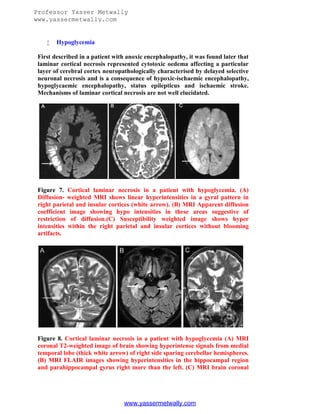

Hypoglycemia

First described in a patient with anoxic encephalopathy, it was found later that

laminar cortical necrosis represented cytotoxic oedema affecting a particular

layer of cerebral cortex neuropathologically characterised by delayed selective

neuronal necrosis and is a consequence of hypoxic-ischaemic encephalopathy,

hypoglycaemic encephalopathy, status epilepticus and ischaemic stroke.

Mechanisms of laminar cortical necrosis are not well elucidated.

Figure 7. Cortical laminar necrosis in a patient with hypoglycemia. (A)

Diffusion- weighted MRI shows linear hyperintensities in a gyral pattern in

right parietal and insular cortices (white arrow). (B) MRI Apparent diffusion

coefficient image showing hypo intensities in these areas suggestive of

restriction of diffusion.(C) Susceptibility weighted image shows hyper

intensities within the right parietal and insular cortices without blooming

artifacts.